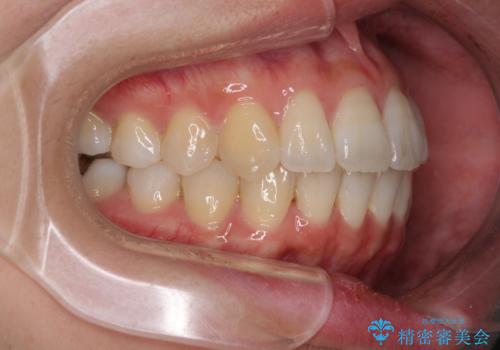

歯列全体の拡大と、歯と歯の間を削ることでスペースを獲得し、インビザラインによる矯正治療を行うこととしました。

骨格的な問題を抱えた左奥以外は比較的早く咬み合わせが改善しましたが、左奥はどこで咬み合えば良いのか分からず、大変不便な思いをされていました。

ゴムかけにご協力いただき、最終的には反対咬合を改善することができ、患者様には大変満足していただきました。